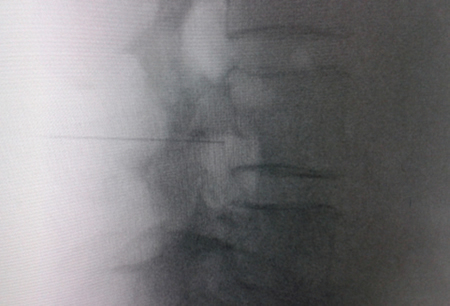

Figure 1